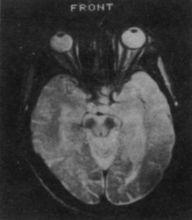

④血及腦脊液常規檢查無異常,CT、MRI檢查也無特徵性所見。